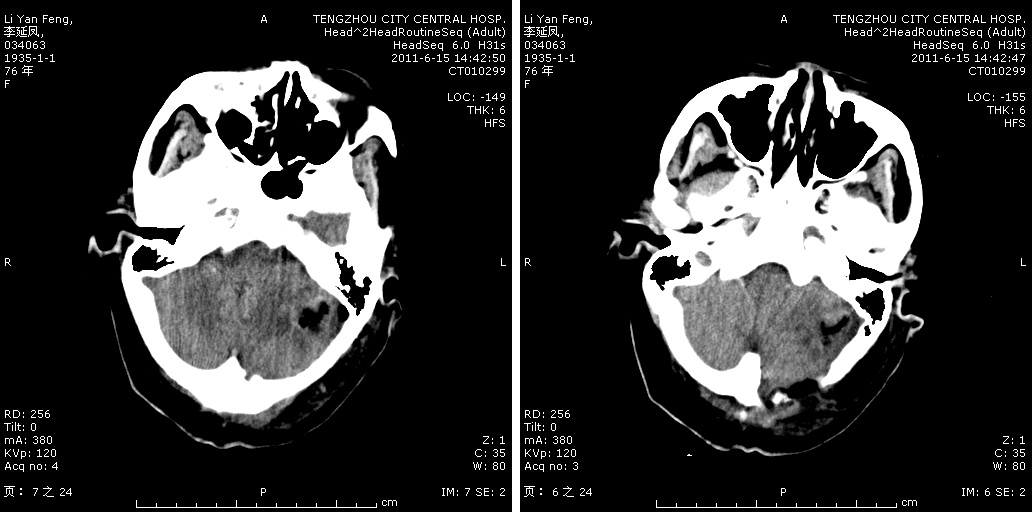

轉(zhuǎn)移瘤切除術(shù)后